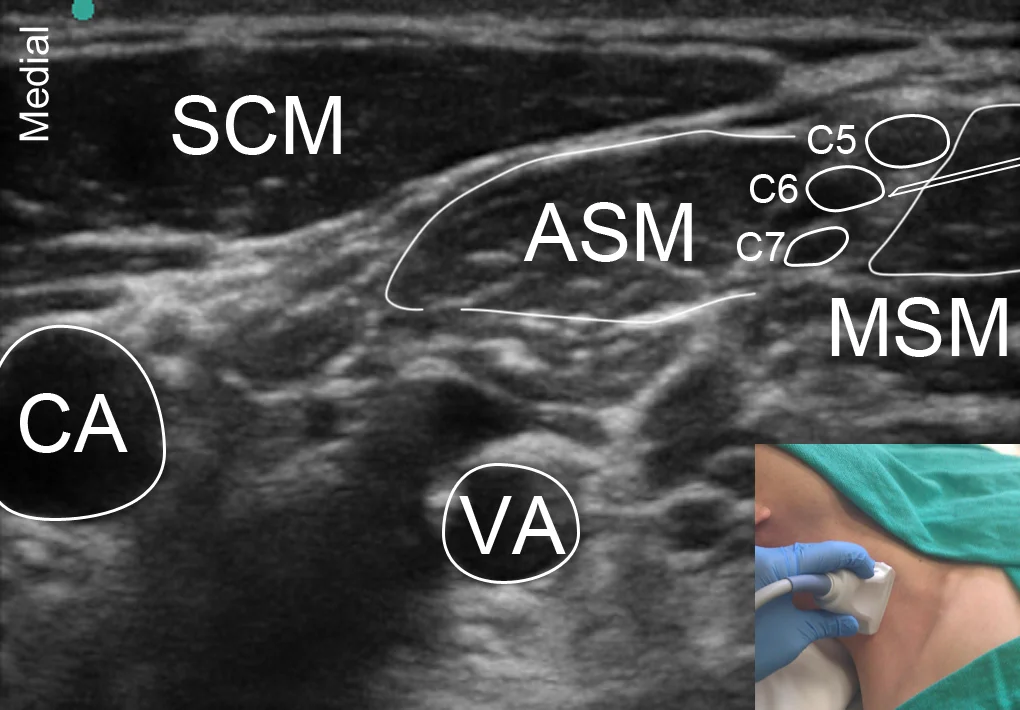

Precision Guided Injections and Interventions